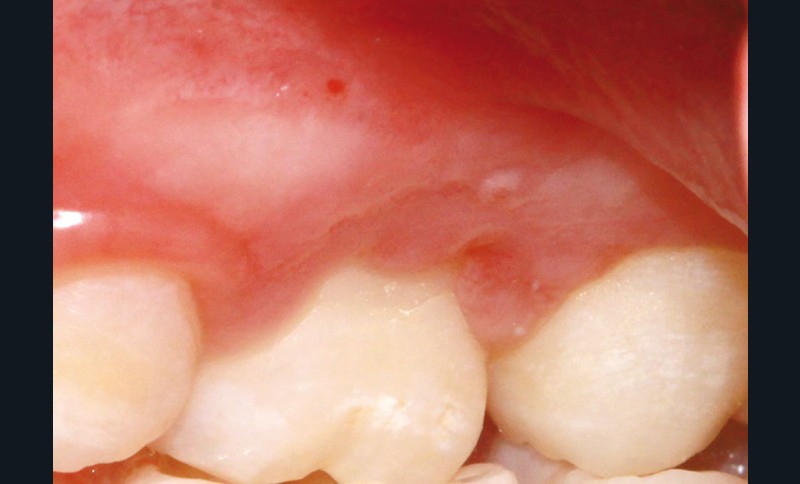

L’examen clinique révèle la présence d’une ulcération végétante, d’environ 1 cm de diamètre, localisée sur les gencives marginale, papillaire et attachée en vestibulaire de 55 et 16, associée à une récession parodontale pour 55. L’ulcération est bien délimitée, indolore et non hémorragique spontanément. Les dents présentent une mobilité physiologique et il n’existe pas d’adénopathie.

En première intention, un gel antiseptique à base de chlorhexidine à 0,12 % est prescrit pendant 8 jours, à raison de deux applications quotidiennes.

Lors du contrôle à une semaine, la situation clinique ne s’est pas améliorée et devant l’aspect…